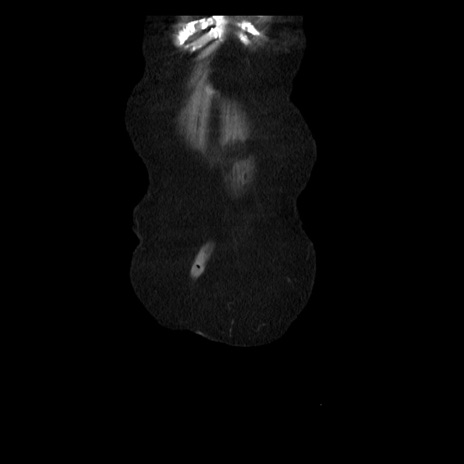

横断像

症例14(冠状断像)

【症例】 90歳代女性

【主訴】 腹痛・嘔吐

【現病歴】今朝から左側腹部痛を認めた。 経過観察していたが、嘔吐を認めたため来院。

【既往歴】 子宮癌術後

【身体所見】 意識清明、BP 127/54mmHg、P 98bpm Sp02 95%(RA)、BT 35.8°C、腹部平坦・軟腸ぜん動音聴取良好、右下腹部圧痛(+) 反跳痛なし

【データ】WBC 9800、CRP 0.46